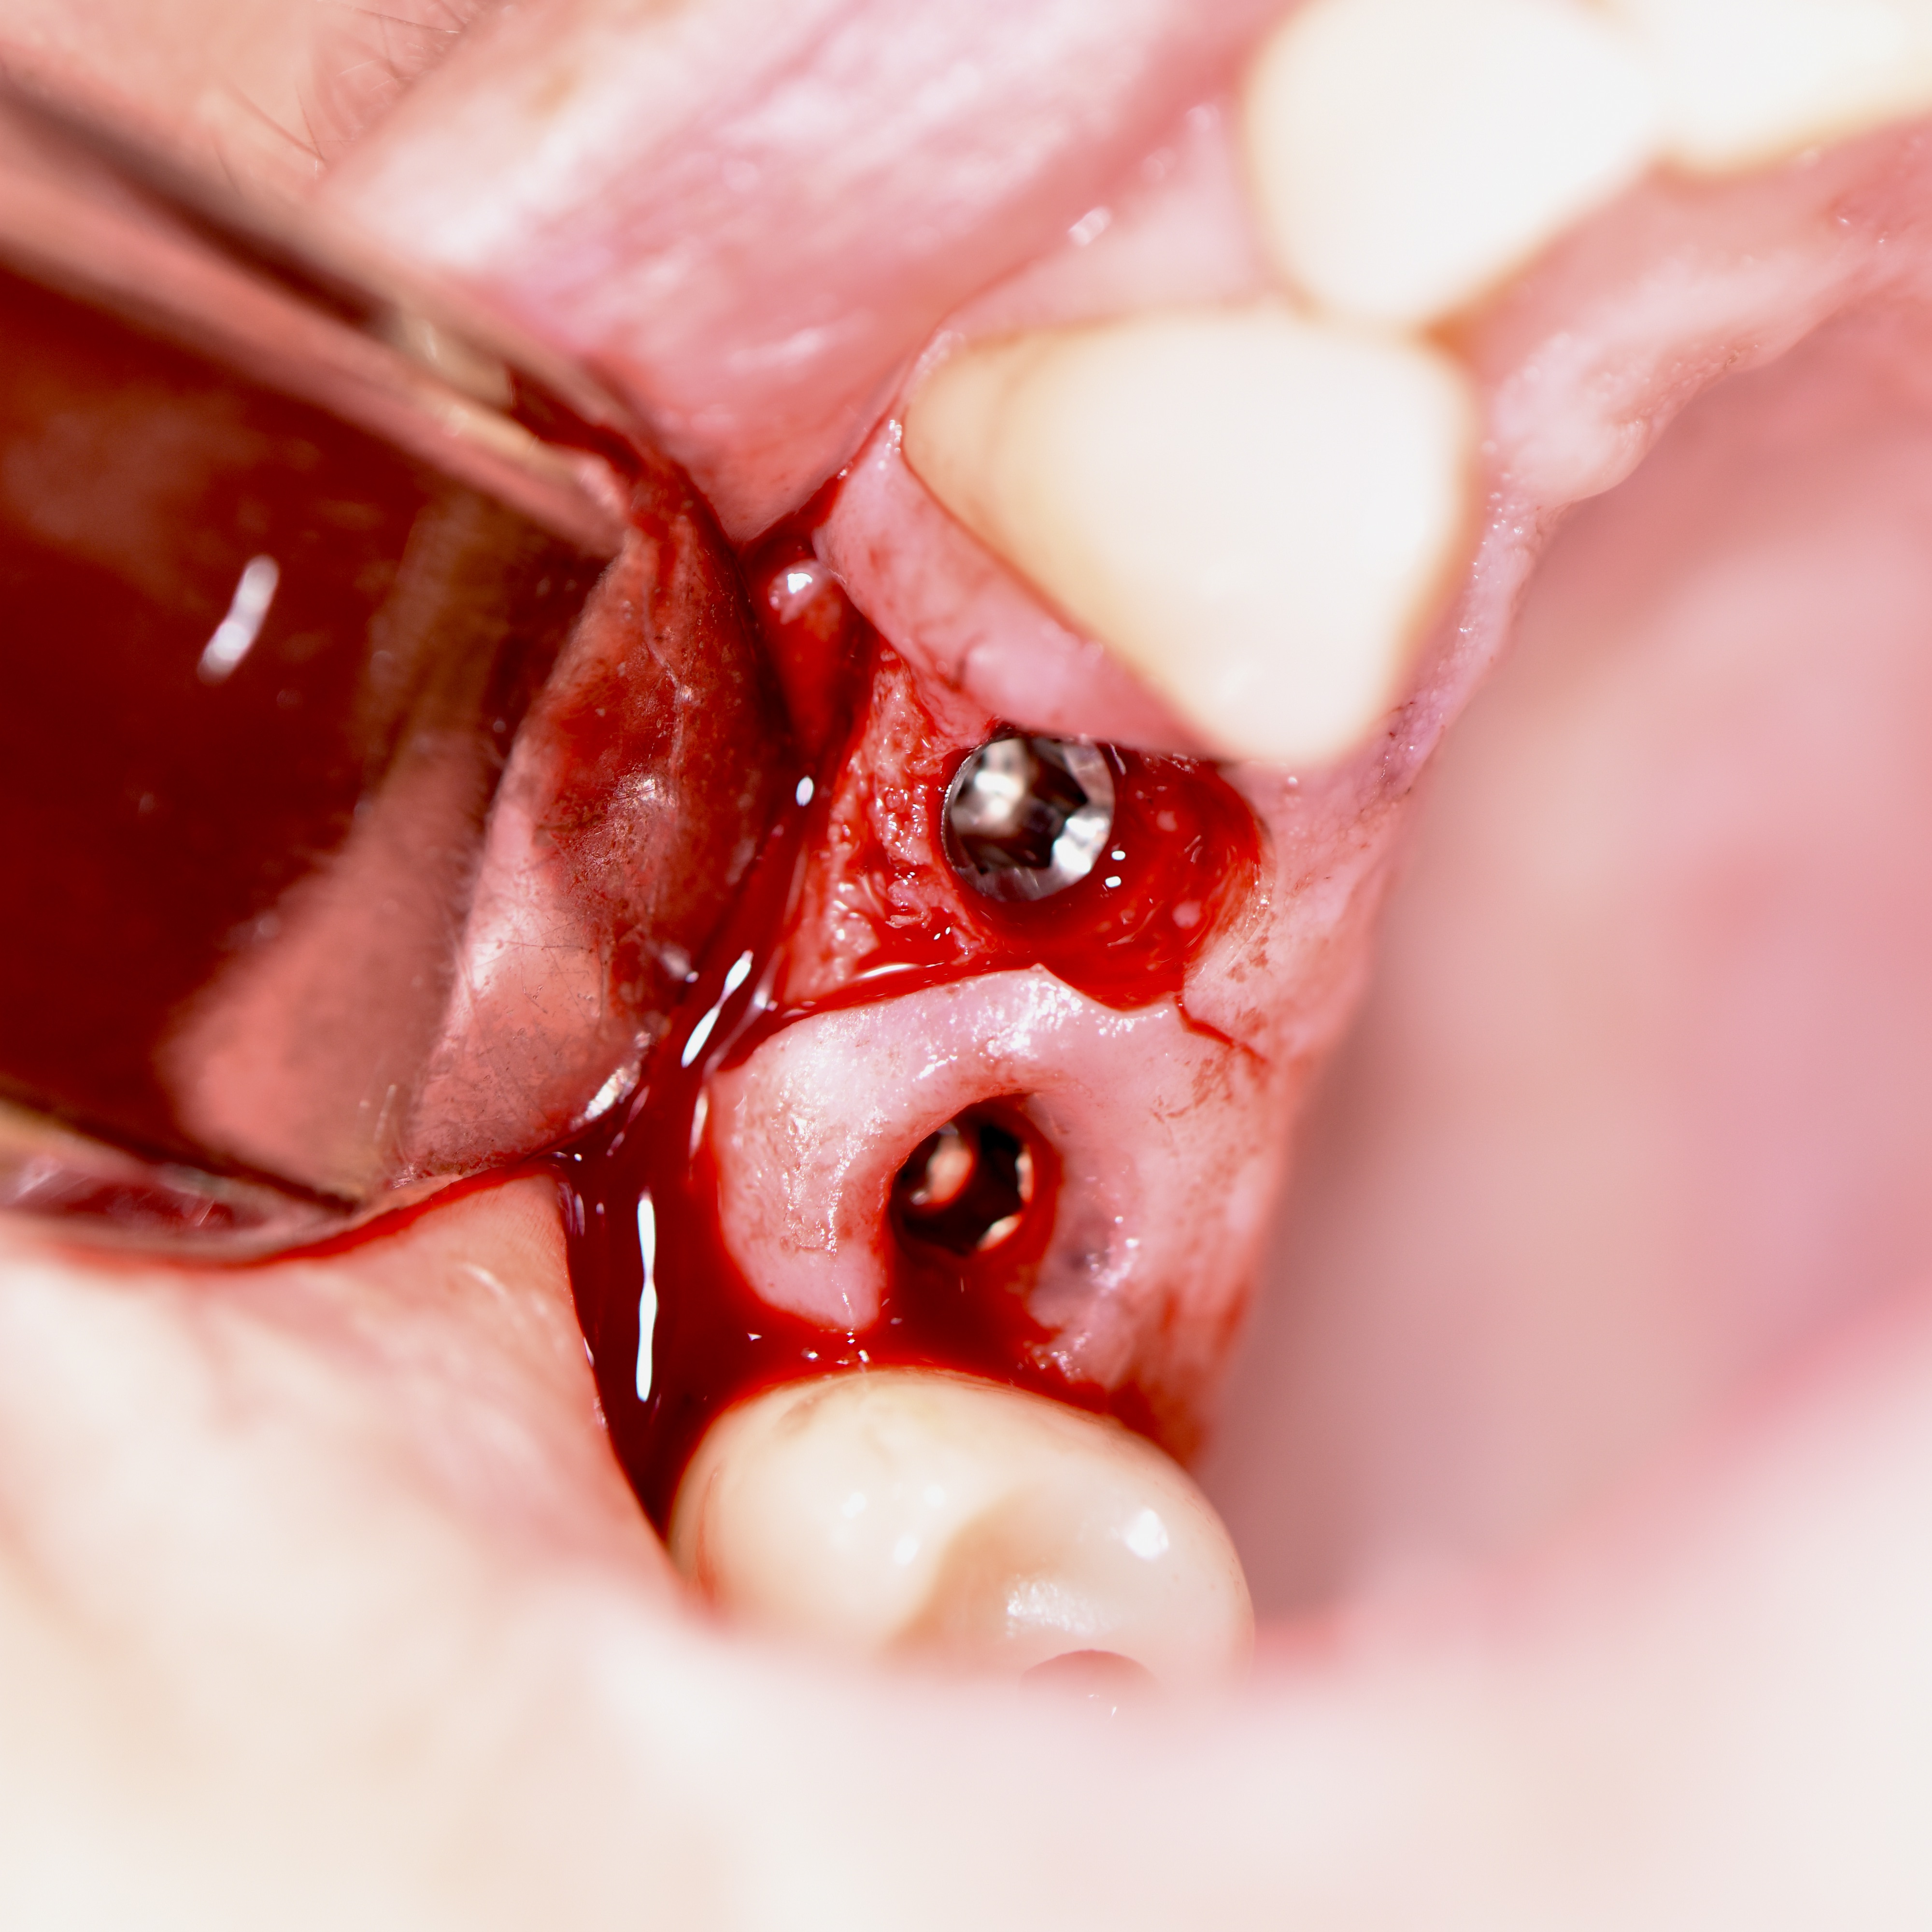

Atraumatic Extraction with Bone Graft